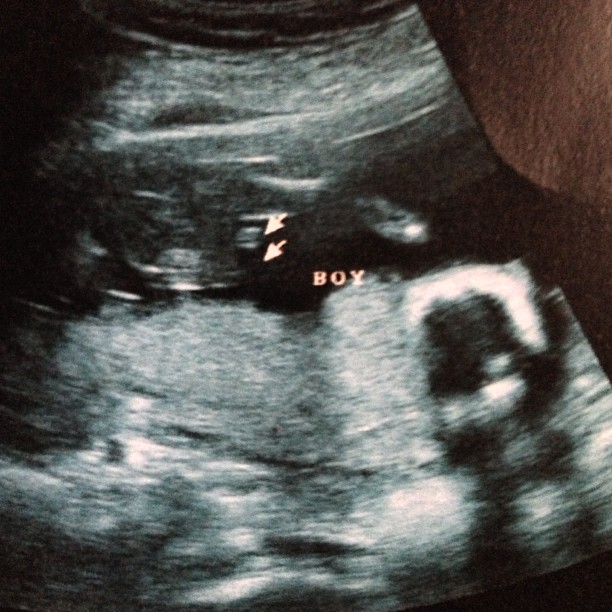

ล่าสุดสาว (11 เมษายน) ตั๊ก บงกช ก็ได้เผยภาพอัลตราซาวด์ลูกในท้องออกมาแล้ว โดยระบุว่า ตั๊ก บงกช ได้ลูกชาย ซึ่งถือเป็นของขวัญในเดือนเกิดของตัวเองพอดี งานนี้ก็มีแฟนคลับมาร่วมแสดงความยินดีกันอย่างคับคั่ง โดยมีคนถามว่า ตั๊ก จะยังตั้งชื่อลูกว่า น้องข้าวหอม อยู่หรือเปล่า ซึ่ง ตั๊ก บงกช ก็ตอบกลับว่า ลูกชายของเธอชื่อ น้องข้าว แต่พ่อของเขาบอกว่าอยากให้ลูกชื่อ น้องข้าวหอม มากกว่า